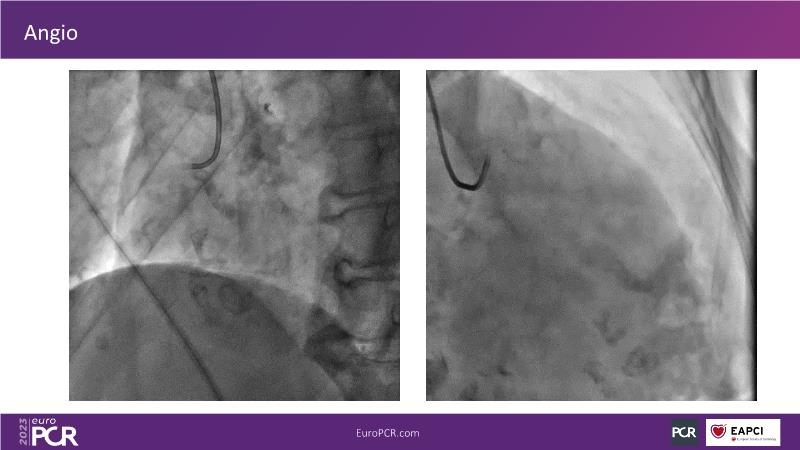

Join this session to explore the advantages of a fully optical approach in optimizing percutaneous coronary intervention (PCI) with the OptoWire III physiology wire and Nipro HF-OCT catheter. Through a practical case, you'll discover the significance of coronary physiology and intravascular imaging in bifurcation PCI and gain insights into how the performance and accuracy of the OptoWire III physiology wire can facilitate fast and reliable decision-making, particularly in side branch jailing scenarios.

- To discover the benefits of a fully optical approach to optimise PCI with OptoWire III physiology wire and Nipro HF-OCT catheter

- To understand how the performance and accuracy of OptoWire III physiology wire can make the difference for fast and reliable decision-making in bifurcations, particularly through side branch jailing